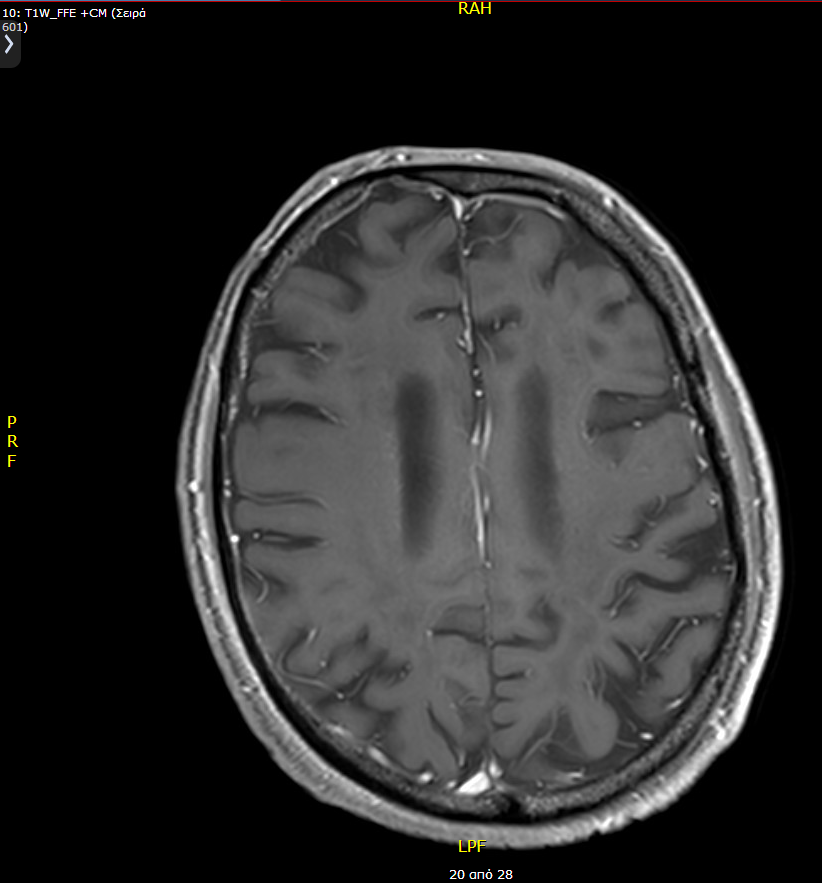

A 38-year old male was admitted to our hospital complaining of progressive memory loss during the last two months. His medical record included heavy smoking (40 pack-years) but was otherwise unremarkable. The results of the neurological examination and laboratory tests were all within normal ranges. An MRI scan of the brain was performed, showing multiple contrast-enhancing space-occupying lesions (Figure 1). The differential diagnosis included brain metastases from some primary tumor such as lung and diffuse multifocal glioma. A thoraco-abdominal CT scan was performed to eliminate the former possibility. Subsequently, a stereotactic biopsy of a single lesion was performed, and the microscopic examination revealed a diffuse astrocytoma, grade II per WHO classification 2007 (Figure 2). At the time of diagnosis, three years ago, we did not perform molecular profiling (IDH mutations, 1p/19q codeletion, ATRX loss, and MGMT methylation status) in central nervous system tumors. Despite the particularly low proliferative index (Ki67: 1-2%), it was decided to be treated aggressively due to high volume disease. He underwent volumetric modulated arc therapy (VMAT) with a simultaneous integrated boost, receiving 54 Gy in 30 sessions with 1.8 Gy per session to the enhancing lesions of the brain and 50 Gy in the peritumoral edema (Figure 3). Concurrent with radiotherapy, he received temozolomide 75 mg/m2. After completing chemoradiotherapy, he continued with adjuvant temozolomide 150 mg/m2 (escalated to 200mg/m2 from cycle two onwards) for 12 months. Since then, he is disease-free with regular MRI/MR spectroscopy imaging (Figure 4). The deterioration of his memory loss halted, and the patient reports no other neurological symptoms.

Figure 4 Follow-up brain MRI three years later from the initial diagnosis showing complete radiological response.